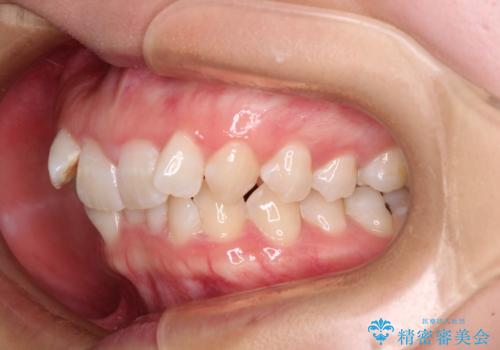

- 上下前歯のデコボコを気にして来院された患者様です。

口元の突出感はあまりなかったものの、デコボコを非抜歯で改善すると出っ歯になる可能性があるため、上下左右の第一小臼歯4本を抜歯し、ワイヤー装置にて矯正治療を行うこととしました。

口元の突出感がない分、奥歯を前方に移動させる必要がありましたが、予定の2年間で無事に治療を終えることができました。